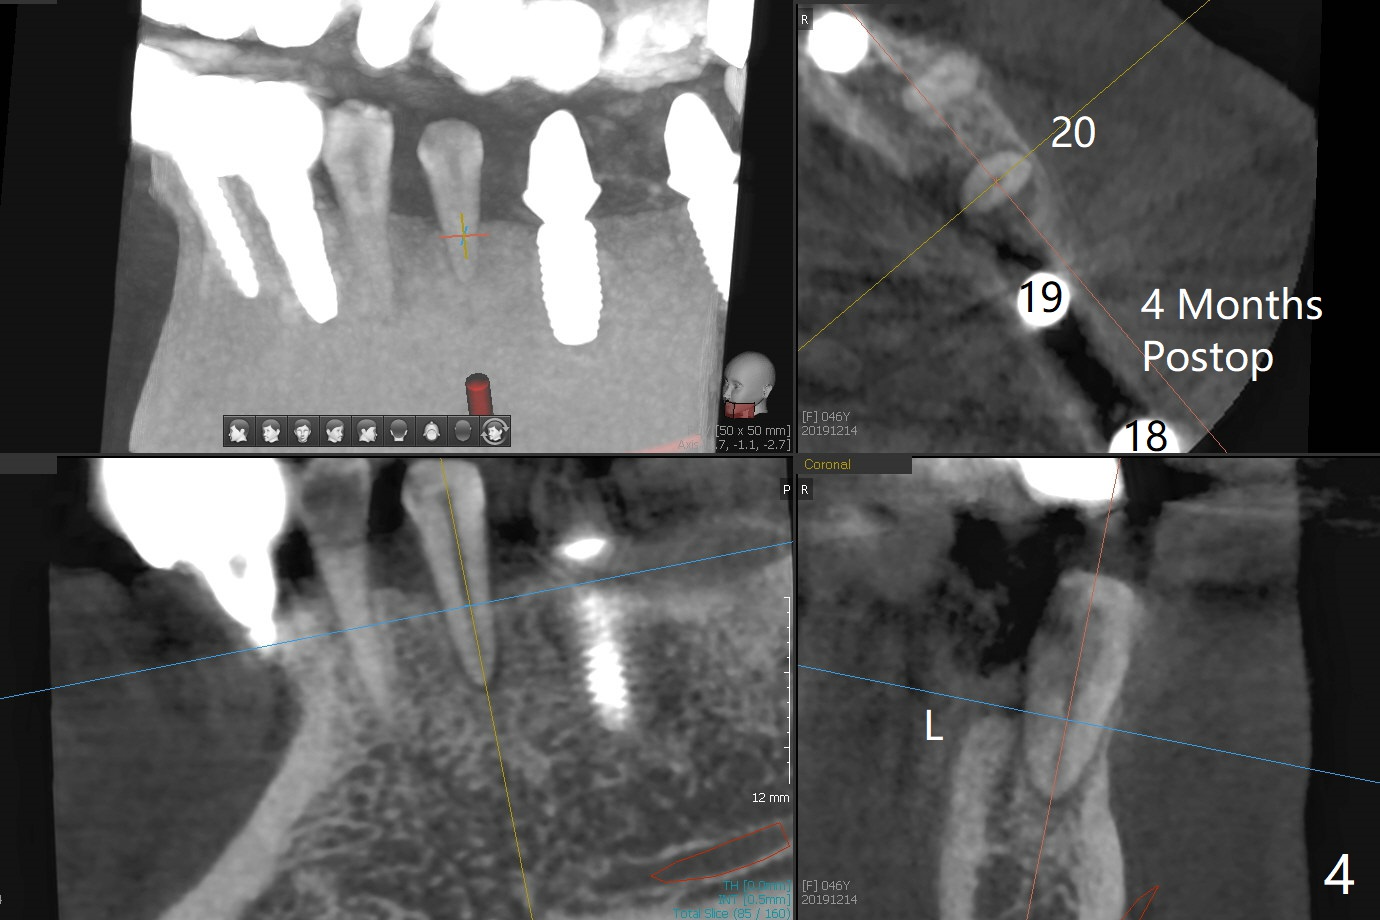

Re-analysis of preop CT reveals extensive bone loss around #18 (Fig.1 (lingual view)). Blood is withdrawn for sticky bone. After implant placement (Fig.2), sticky bone is placed at #18 (Fig.3 red dashed line (yellow: superior border of the Inferior Alveolar Canal)). PRF membrane and an immediate provisional FPD (#18-20) further keep the bone graft in place for healing. Four months postop, the patient reports difficulty in mastication on the left and requests extraction of the tooth #20 for implant (Fig.4). The implant will be placed lingually, while socket shield will be performed buccally (Fig.5 S) to keep bone graft in place. The implant at #19 is equicrestal (Fig.6); the one at #18 is apparently supracrestal buccally (Fig.7). Since there is a lot of scattering from nearby crowns, the implant at #20 will be placed free hand. To overcome the thick dense lingual plate (Fig.8 L), osteotomy is initiated (Fig.9 red line) in the middle of the lingual wall of the extraction socket (black area) on the top of the socket shield (S). After the last drill (3.5x11.5 mm, Fig.10 pink) and before 4x11.5 mm implant, use Lindamann bur to remove the coronal portion of the lingual plate (Fig.11 red line) to prevent implant buccal deviation.